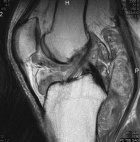

43 y/o male w 5 years of chronic R knee pain, worsening over the past 3 years. Feels like “crunching marbles”. Pain at night and worse with activity. No weight loss, fevers/chills. No systemic complaints.

PE: R knee effusion; crepitus, palpable masses near popliteal fossa, mild dec R knee ROM secondary to pain, neurovascularly intact, 5/5 motor.